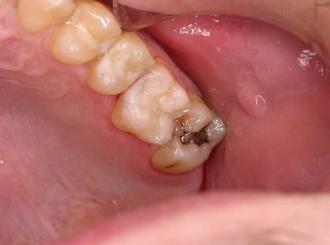

This patient has a similar problem, a decayed amalgam filling on the upper left.  The old filling was

replaced with white bonded filling.  The back tooth will most likely need a new filling as well.